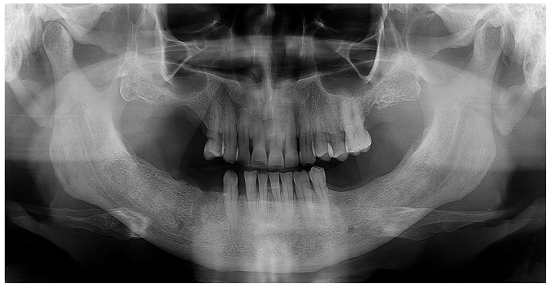

The patient was referred to the Clinical Oncology Department and underwent chemotherapy with paclitaxel 60 mg/m2. After a 4-month follow-up, the patient was asymptomatic and the x-ray showed signs of bone neoformation (Figure 4).

Radiographically, most cases of metastatic lesions present as osteolytic areas poorly defined with a “moth eaten” appearance.2 The imaging study of our patient was quite different presenting a well-defined margin of the lesion. Consequently, the hypothesis of metastatic SCLC of the mandible was not initially taken into account. Based on the clinical/radiograph findings and previous history of the first premolar’s exodontia, the lesion was initially considered as an odontogenic lesion.